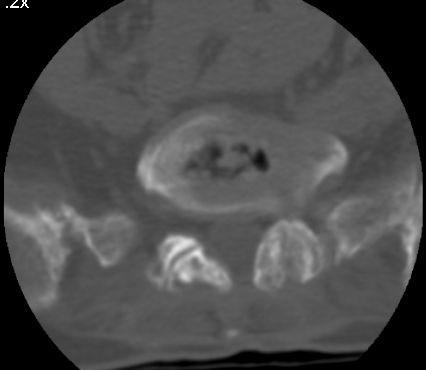

以下是引用余辉在2007-9-4 21:00:00的发言:[br]椎体棘突有点异常(像是被切割了),不知有否手术史,如椎体融合术等。单纯的退行性变可以出现椎间隙变窄,但同时一般会出现椎体上下缘的硬化增生,且椎体间完全融合的机率更小,本例椎体完全融合且椎体上下皮质缘破坏掉了,如果没有手术史,就应该考虑椎间盘炎性病变了,且椎体棘突及棘间韧带的变化也并不是不支持这个,多数小关节也融合了,且其形态也容易让人联想到如强脊炎及类风关等病变。[br][br][本贴已被 余辉 于 2007-9-4 21:03:55 修改过]

以下是引用chry3在2007-9-4 20:42:00的发言:[br]椎间盘病史?是什么样的病史,无双下肢放射痛,那就不是椎间盘突出了。是感染、什么性质的?[br]从图象看椎间隙消失,椎间盘组织未见,锥体滑脱是因为椎间盘溶解造成的[br]l4、5椎体骨质结构未见异常,l5上缘是l4的长期压迫所致[br]还是考虑椎间盘感染,结核。[br]